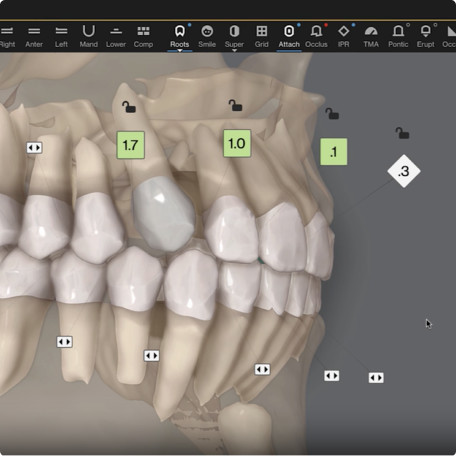

Auto-generates a 3D model with roots, crown, and bone for more-informed treatment planning.

See patients' roots, crowns, and bone in one auto-generated 3D model with new CBCT integration.

Shows you real root renderings and bone visualizations based on actual scan data.

Four views in one integrated platform to enhance treatment planning.

Roots and gingiva

Roots only

Roots with semitransparent bone

Roots and bone

Roots and gingiva

Roots only

Roots with semitransparent bone